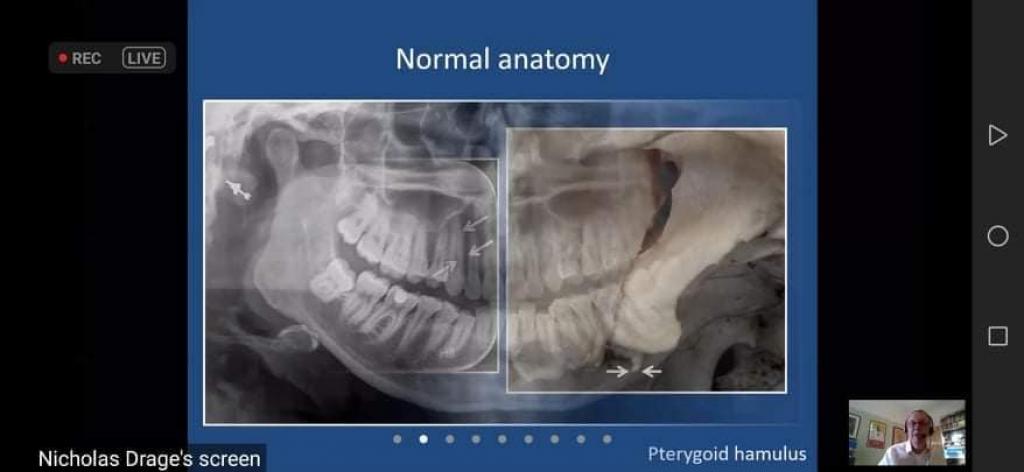

استضافت كلية طب الأسنان في جامعة الموصل الاستشاري ( نيكولاس درييج) من جامعة كارديف / المملكة المتحدة في محاضرة إلكترونية تفاعلية مهمة عن التشخيص التفريقي للآفات المعتمة في الفكين، بإشراف الاستاذ المساعد الدكتور ريان سالم حامد عميد الكلية ،يوم الأربعاء ١٤/ نيسان/٢٠٢١، حضرها عدد من أطباء الأسنان ومن تدريسيي وطلبة الكلية .

تطرقت الورشة الى أهمية هذا التشخيص في تحديد الحالات و الآفات البسيطة و المعقدة و رسم خطط العلاج المناسب.